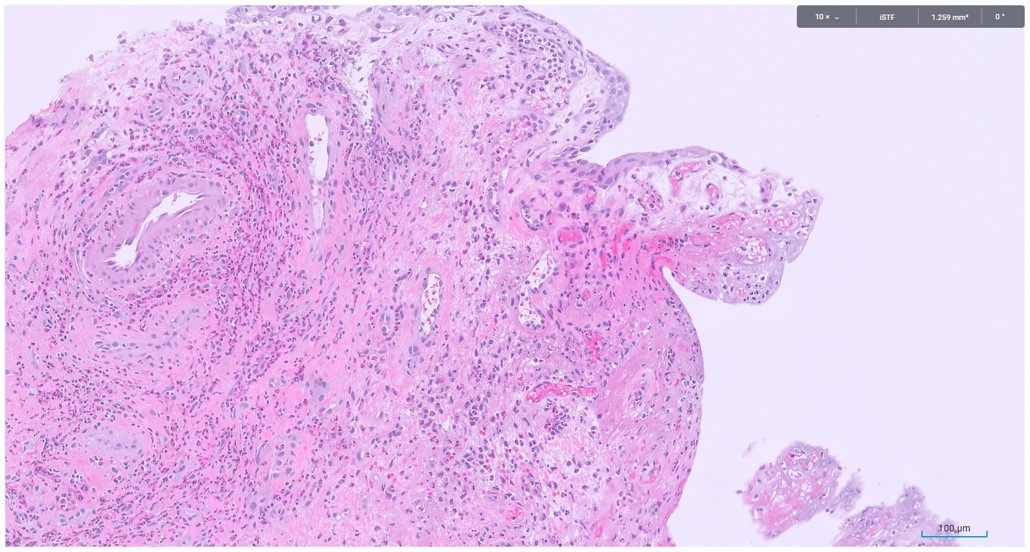

Microscopic image possibly detecting cancerous areas in human tissue

What is the most likely diagnosis?

1. Radiation cystitis

2. Cystitis cystica

3. Invasive urothelial carcinoma

4. carcinoma in situ

Radiation cystitis